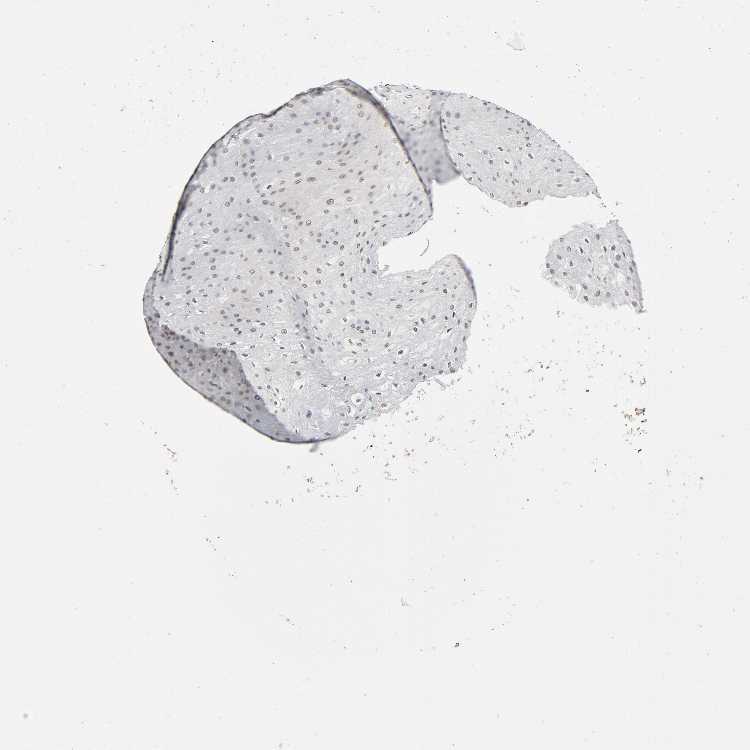

ESOPHAGUS - Antibody stainingi

Antibody staining in the annotated cell types in the current human tissue is reported as not detected, low, medium, or high, based on conventional immunohistochemistry profiling in selected tissues. This score is based on the combination of the staining intensity and fraction of stained cells.

Each image is clickable and will lead to virtual microscopy that enables deeper exploration of all samples and also displays staining intensity scores, fraction scores and subcellular localization as well as patient and tissue information for each sample.

Antibody HPA015270Antibody CAB004038

Squamous epithelial cells LowNot detected